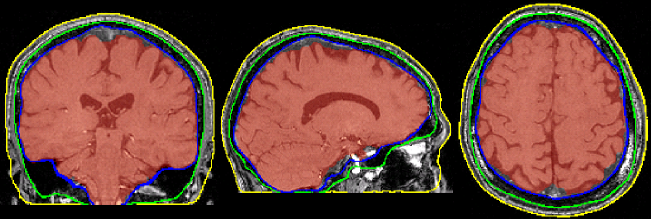

BET (Brain Extraction Tool) deletes non-brain tissue from an image of the whole head. It can also estimate the inner and outer skull surfaces, and outer scalp surface, if you have good quality T1 and T2 input images.